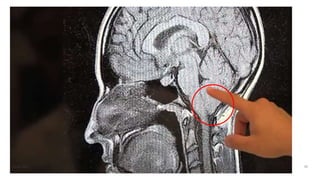

Aqueduct stenosis

Arnold-Chiari malformations

◦Portion of cerebellum and brainstem herniating into cervical spinal

canal, blocking the flow of CSF into the posterior fossa.